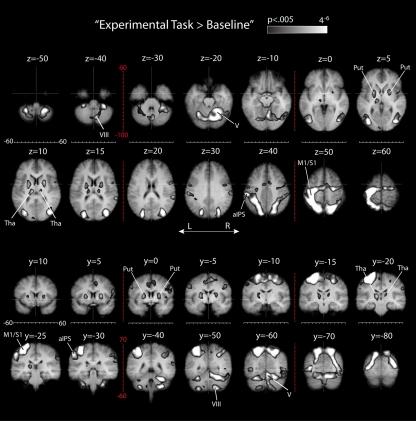

Neuropsychological evidence suggests that different brain areas may be involved in movements that are directed at visual targets (e.g., pointing or reaching), and movements that are based on allocentric visual information (e.g., drawing or copying). Here we used fMRI to investigate the neural correlates of these two types of movements in healthy volunteers. Subjects (n = 14) performed right hand movements in either a target-directed task (moving a cursor to a target dot) or an allocentric task (moving a cursor to reproduce the distance and direction between two distal target dots) with or without visual feedback about their hand movement. Movements were monitored with an MR compatible touch panel. A whole brain analysis revealed that movements in allocentric conditions led to an increase in activity in the fundus of the left intra-parietal sulcus (IPS), in posterior IPS, in bilateral dorsal premotor cortex (PMd), and in the lateral occipital complex (LOC). Visual feedback in both target-directed and allocentric conditions led to an increase in activity in area MT+, superior parietal-occipital cortex (SPOC), and posterior IPS (all bilateral). In addition, we found that visual feedback affected brain activity differently in target-directed as compared to allocentric conditions, particularly in the pre-supplementary motor area, PMd, IPS, and parieto-occipital cortex. Our results, in combination with previous findings, suggest that the LOC is essential for allocentric visual coding and that SPOC is involved in visual feedback control. The differences in brain activity between target-directed and allocentric visual feedback conditions may be related to behavioral differences in visual feedback control. Our results advance the understanding of the visual coordinate frame used by the LOC. In addition, because of the nature of the allocentric task, our results have relevance for the understanding of neural substrates of magnitude estimation and vector coding of movements.

神经心理学证据表明,不同的大脑区域可能参与指向视觉目标的运动(例如,指向或伸手),以及基于以自我为中心的视觉信息的运动(例如,绘制或复制)。在这里,我们使用 fMRI 来研究健康志愿者这两种类型的运动的神经相关性。受试者(n=14)在手有或没有关于其手部运动的视觉反馈的情况下,在手定向任务(将光标移动到目标点)或以自我为中心的任务(将光标移动到两个远程目标点之间的距离和方向)中执行右手运动。运动由与磁共振兼容的触摸面板监测。全脑分析显示,在以自我为中心的条件下进行运动导致左侧顶内沟(IPS)底部、IPS 后部、双侧背侧运动前皮质(PMd)和外侧枕叶复合体(LOC)的活动增加。在目标定向和以自我为中心的条件下的视觉反馈都导致 MT+、上顶枕叶皮质(SPOC)和 IPS(均为双侧)的活动增加。此外,我们发现视觉反馈对目标定向与以自我为中心条件下的大脑活动的影响不同,特别是在前运动辅助区、PMd、IPS 和顶枕叶皮质。我们的结果与以前的发现相结合,表明 LOC 是自我为中心的视觉编码所必需的,SPOC 参与视觉反馈控制。目标定向和以自我为中心的视觉反馈条件之间的大脑活动差异可能与视觉反馈控制的行为差异有关。我们的结果提高了对 LOC 使用的视觉坐标系的理解。此外,由于以自我为中心任务的性质,我们的结果与对运动的幅度估计和向量编码的神经基质的理解有关。